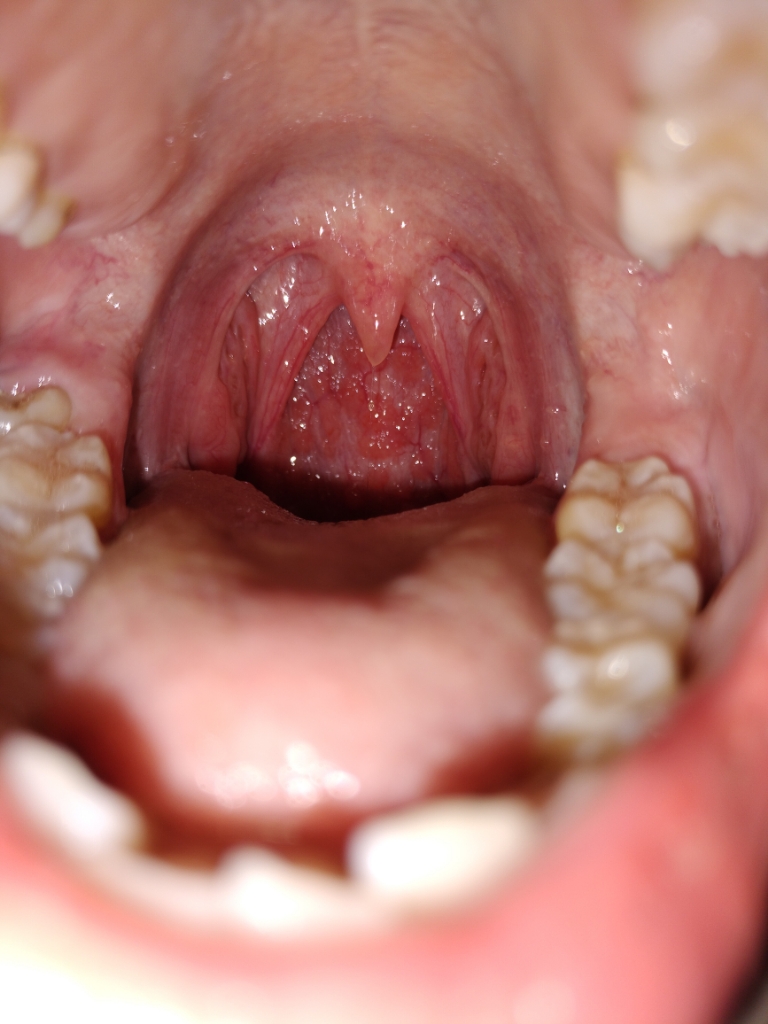

Cho e hỏi đây có phải viêm họng hạt không ak